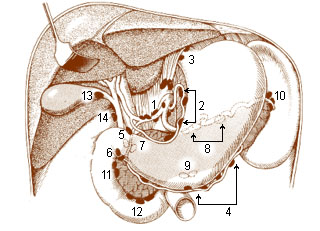

Hilar Lymph Nodes Map

mavink.com

mavink.com

Hilar Lymph Nodes Map

mavink.com

mavink.com